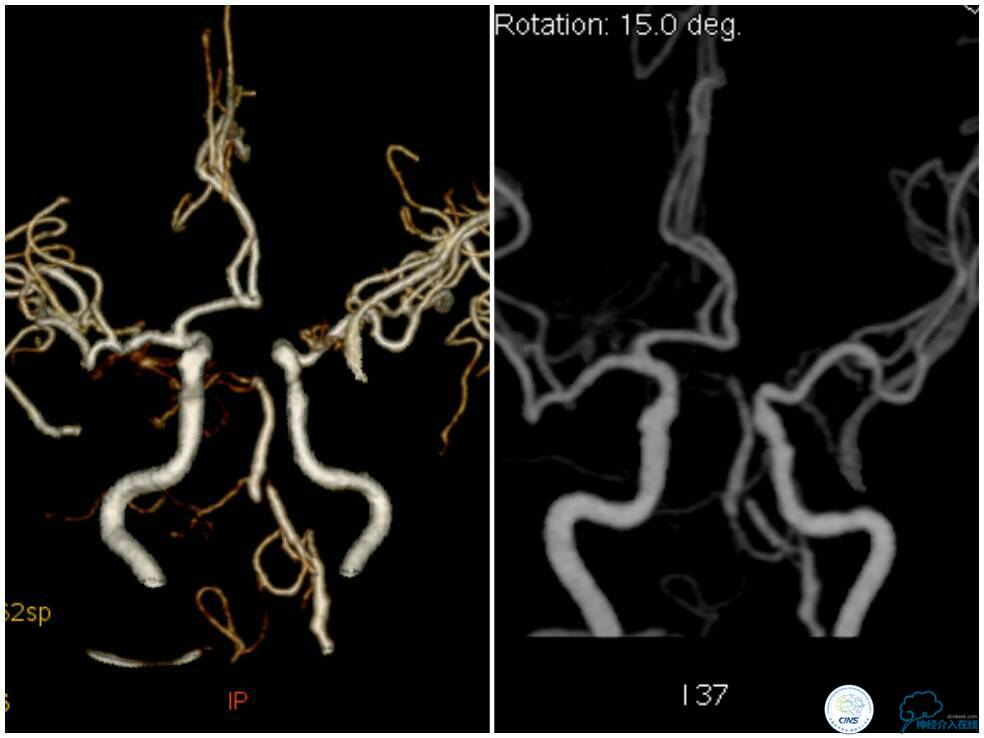

血栓弹力图检查:AA抑制率98.2%、ADP抑制率47.7%。颅内CTA及后循环CT灌注检查提示:右椎动脉V4段未见显影,左椎动脉与基底动脉汇合处重度狭窄,右椎动脉V4段在汇合点以下有显影(图5);双侧小脑半球低灌注,右侧为著(图6)。

图5